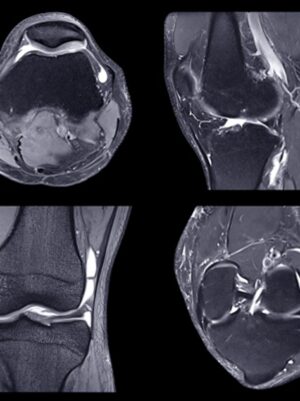

Knee

Patterns of Knee Injury – Donald Resnick, MD

Anterior Knee Pain and Patellofemoral Maltracking – Mini Pathria, MD

MRI of the Knee – How Important are the Corners? – Lawrence M. White MD, FRCPC

Menisci and Cruciates – Is There Anything New I Need to Know? – Christine B. Chung, MD

Imaging of Cartilage and Cartilage Repair – What Does My Surgeon Need to Know? – Richard Kijowski, MD

Cysts, Bubbles and Bursa – the Spaces Around the Knee – Mark D. Murphey, MD

Scroll with the Experts – Knee – Christine B. Chung, MD